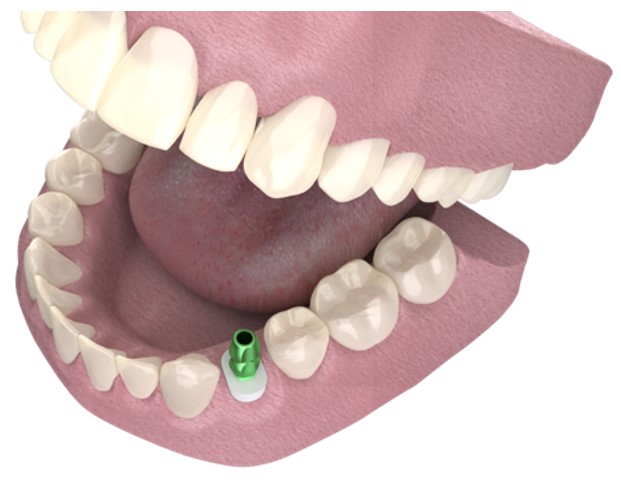

Pasul 6 – Procesul de instalare a pilonului de vindecare personalizat

Instalează bontul personalizat de vindecare în implant, utilizând șurubul de reținere disponibil împreună cu bontul temporar utilizat.

Instalează bontul personalizat de vindecare în implant, utilizând șurubul de reținere disponibil împreună cu bontul temporar utilizat.

Evaluează potrivirea clinică și radiografică adecvată cu implantul.

Umple orificiul de acces cu șurub cu un prim strat de bandă de teflon sterilă sau alt material adecvat.

Umple spațiul liber rămas al orificiului de acces cu șurub cu material compozit și fotopolimerizare.

Evacuează distanța ocluzală adecvată a bontului personalizat de vindecare și, dacă este necesar, reduce înălțimea acestuia.

Acest proces poate fi efectuat în momentul plasării implantului (protocolul cu o etapă) sau în stadiul descoperirii implantului.